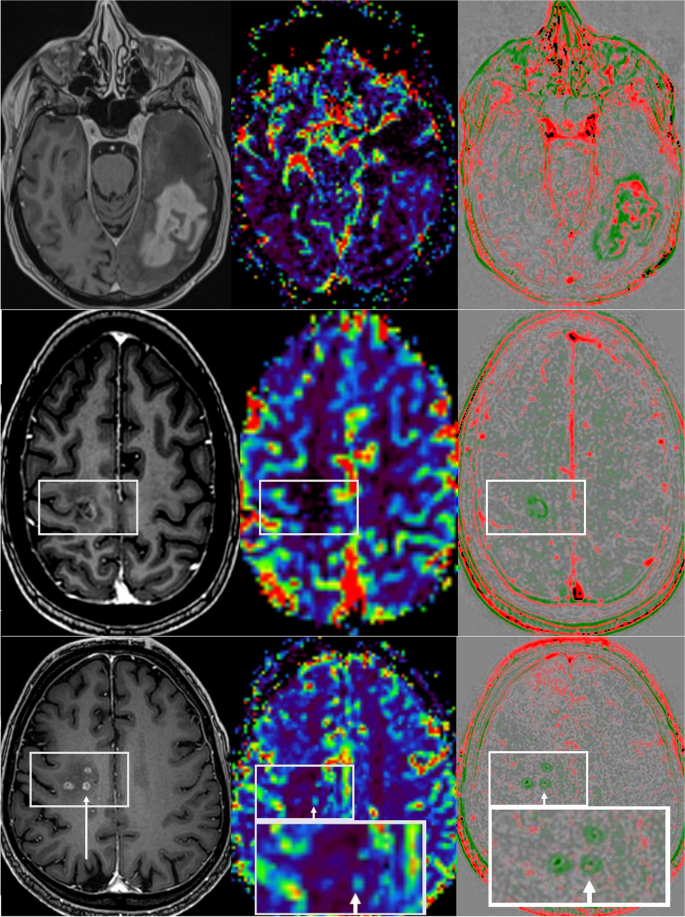

Области снижения интенсивности wash-out (красные) коррелируют с активной опухолевой тканью (рис.4), области повышения интенсивности wash-in (зеленые) — с некрозом или фиброзом (рис.5).

Рис.5. Оценка терапии глиобластомы. Вверху: 200% прогресс объема за 6 недель наблюдения. МР-перфузия (средняя) не показала локальной гиперперфузии. Быстрое вымывание (справа) выявило участки повышенного быстрого вымывания (красный). Середина: Типичные посттерапевтические изменения без гиперперфузии и вымывания, но смываемые (зеленые). Внизу: Лучевой некроз (3-месячное наблюдение было стабильным) с менее активными опухолевыми клетками с пузырчатым видом небольших контрастных поражений и минимальной гиперперфузией (стрелка), а также минимальными кольцеобразными вымывами с красной точкой (стрелка). Слева: Т1-взвешенные изображения с усилением контраста; средняя карта rCBV МР-перфузии; Справа: карта быстрого вымывания.